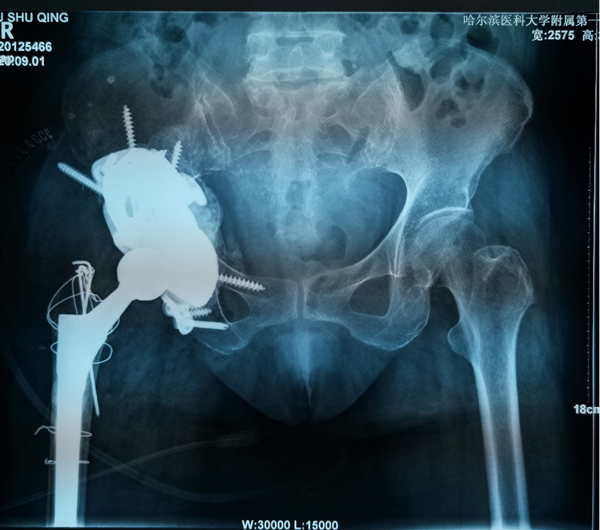

70岁的刘阿姨15年前因股骨头坏死进行了全髋关节置换手术。五年前右腿开始有明显的缩短,髋部疼痛也逐渐加重,来到哈医大一院时已经无法行走。经影像检查,患者15年前采用水泥固定髋臼杯,金属头和聚乙烯髋臼杯十数年的摩擦产生的聚乙烯碎屑已经导致髋臼巨大的骨缺损,假体上移,不仅髋臼,甚至坐骨、髂骨都有骨溶解,属于Paprosky·3B型髋臼侧骨缺损。此类疾病的治疗主要采用三翼髋臼假体(Triflange)。由于患者髋臼骨缺损巨大,特别是在髋臼上部存在巨大的空洞型缺损,传统的Triflange假体不能满足刘阿姨髋臼的稳定支撑和重建,且患者骨质疏松,传统假体骨长入能力难以满足要求。

骨科一病房数字骨科负责人耿硕教授在详细了解患者情况后,决定为患者进行个性化的金属3D打印技术。定制化3D打印髋臼Triflange假体相比于传统假体有以下优点: 3D打印Triflange假体三个翼面通过螺钉分别固定在髂骨,耻骨和坐骨上提供了稳定的初始固定;金属3D打印拥有更好的孔隙率,有助于后期骨长入稳定固定;个性化的术前设计,实现了垫块和臼杯一体的轻量化支撑,更好地填充上方骨缺损重建髋关节的稳定性,此外为应对术中可能的意外情况,还可3D打印不同大小的垫块。

为了确保手术顺利,手术前耿硕根据患者的影像数据,经过三维重建,真实复原了患者的右髋关节和盆骨模型。借助这一模型,耿硕可以全面精准地了解患者的关节结构,骨质情况等重要信息,为术前制订精确的手术方案提供了重要依据。手术当日,耿硕手术团队按照术前模拟,顺利的将金属假体精准地安放在髋关节内。经过一周的康复,患者已顺利下地行走并康复出院。